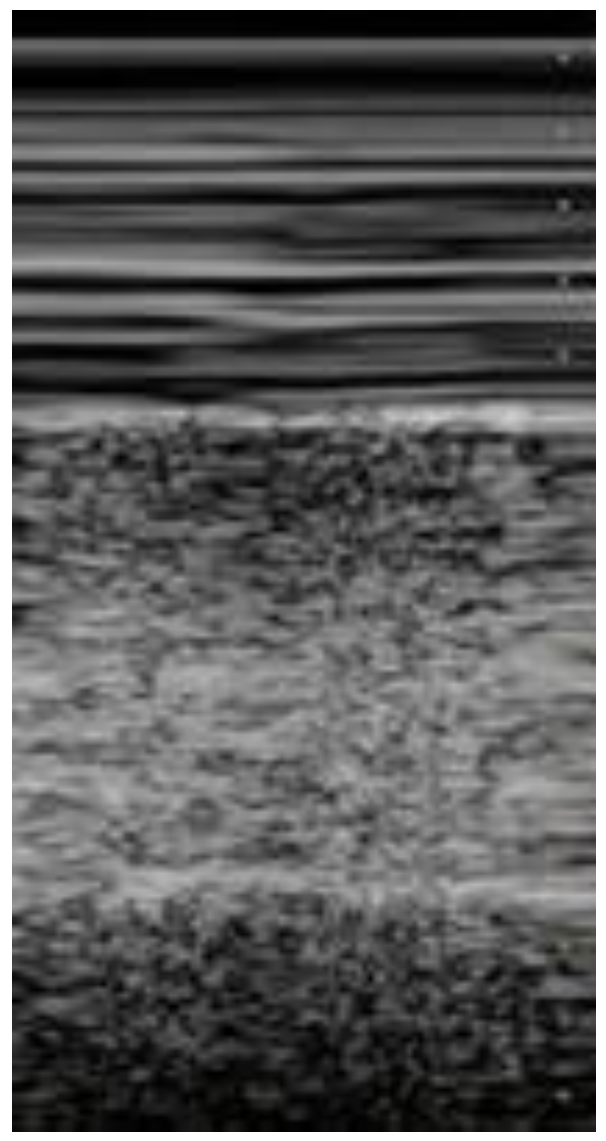

| Seashore sign (Figure 5) | The pleura is represented by horizontal artifacts and the underlying lung has a sandy pattern. | Normal finding |

| Barcode sign (sign of the stratosphere) (Figure 6) | Both the pleura and the lung appear as horizontal artifacts | PNX |